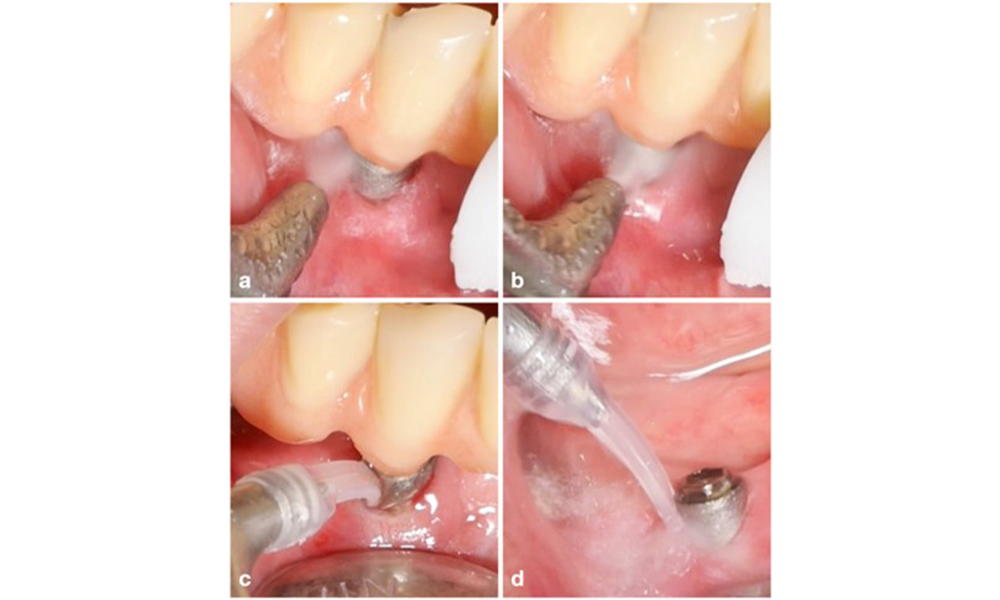

La prise en charge de la péri-implantite sur les implants jugés traitables consiste en une phase non chirurgicale, qui est souvent suivie d'une intervention chirurgicale. Pour l'approche non chirurgicale, des mesures similaires à celles appliquées pour le traitement de la mucosite péri-implantaire sont utilisées ; sur la base d'expériences de laboratoire, les dispositifs d'aéropolissage avec une buse sous-gingivale semblent offrir certains avantages en termes d'élimination du biofilm, par rapport aux instruments manuels ou à ultrasons (Herrera et al. 2023 ; Moharrami et al. 2019 ; Ronay et al. 2017) (figure 9).